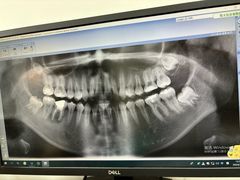

• -上海市青浦区中医医院

匿名用户 | 24-12-06

平凡水水 | 24-08-27